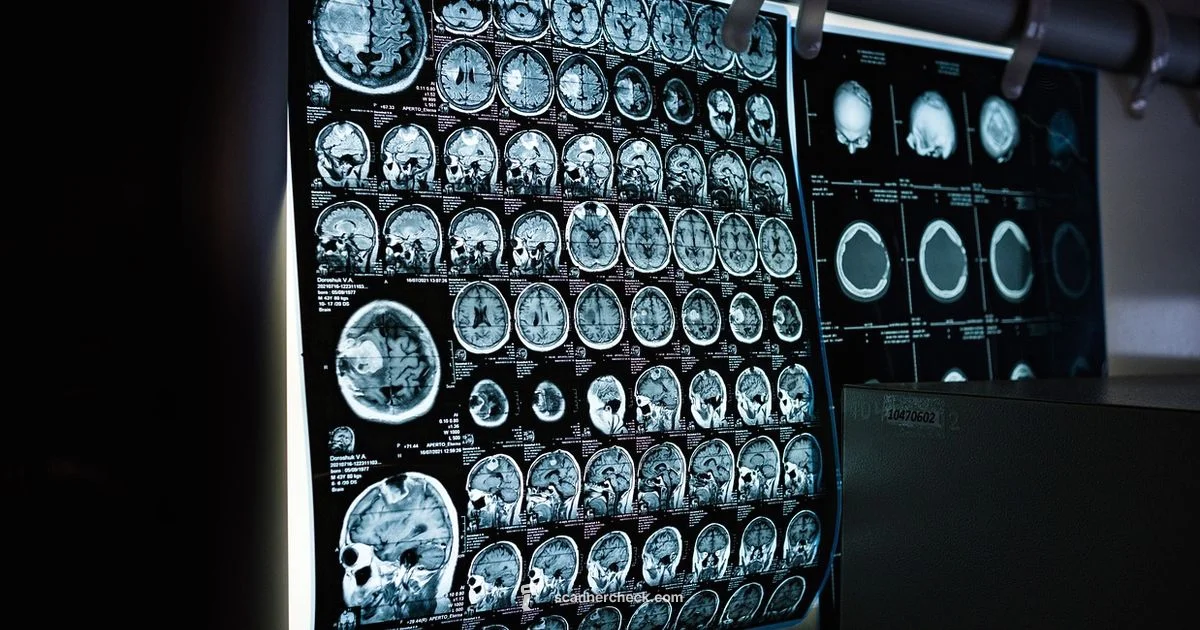

Learn what brain scans are, when they’re used, and how MRI, CT, and other imaging options help diagnose and monitor brain health. This guide explains preparation, modalities, safety, and choosing the right scan for patients and caregivers.

Brain scan is a medical imaging test that generates visual representations of the brain to help diagnose conditions, guide treatment, or monitor brain health.

If you are wondering what scan is for the brain, the answer is that these imaging tests provide critical information about brain structure and activity that helps clinicians diagnose conditions, plan treatment, and monitor changes over time. Brain scans reveal abnormalities such as tumors, bleeding, scar tissue, and areas of reduced or abnormal function that physical exams alone may miss. They also aid in evaluating developmental issues in children and tracking progression in neurodegenerative diseases. In many cases, imaging is used alongside neurological exams, blood tests, and cognitive assessments to form a complete picture of brain health. Understanding the purposes of different scans helps patients engage more effectively with their care team and participate in decisions about next steps. According to Scanner Check, the goal is to match the test to the clinical question while keeping patient safety front and center.

Brain imaging encompasses several techniques, each with strengths and tradeoffs. Magnetic resonance imaging (MRI) uses strong magnets and radio waves to generate high-resolution pictures of soft tissue, excellent for detecting subtle lesions and mapping brain structures. Computed tomography (CT) relies on X-ray measurements to produce fast cross-sectional images, which is invaluable in emergencies like trauma or suspected hemorrhage. Positron emission tomography (PET) assesses metabolic activity by tracking radiotracers, helping distinguish active disease from scar tissue when anatomy alone is unclear; it is often paired with CT or MRI for precise localization. Functional MRI (